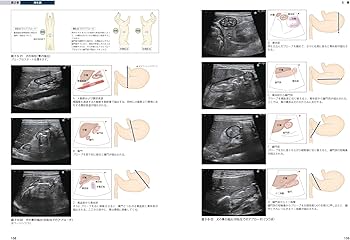

犬と猫の基本的な画像診断に関する専門書。- タイトル: 犬と猫のベーシック画像診断学- ISBN: 978-48931-368-7- 内容: 犬と猫の基本的な画像診断に関する専門書ご覧いただきありがとうございます。卒業が近いので出品させていただきます。ほとんど使用しておりません#獣医| カテゴリー: | 本・雑誌・漫画>>>本>>>健康・医学 |